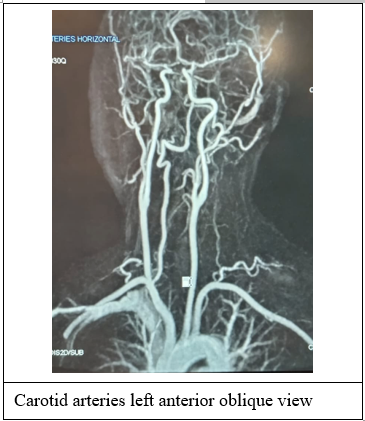

However, following this adventure, the patient suffered another episode of transient visual loss, this time of longer duration and more severe than before, lasting over 30 seconds and exhibiting a greater disability. The patient made a spontaneous recovery and consulted another ophthalmologist, who made the diagnosis of amaurosis fugax and suggested the additional investigation of ultrasonography of the carotid arteries. This was duly carried out without significant findings of wall-thickening, mural thrombi, atherosclerotic ulceration or aneurysmal dilatation. (Figure 2) Repeat of the MRI stroke package (Figure 3) and echocardiogram showed no change from the findings two years ago. Our consensus now is to go one step further and do a trans-esophageal echocardiogram (TEE) with air microbubbles as contrast. This was carried out under general anaesthesia the next day, with the finding of a patent foramen ovale which was successfully closed with a percutaneous transcatheter-deployed occluding device. (Figure 5)

Figure 2: MR angiogram showing patient’s almost unblemished arterial supply to the brain.